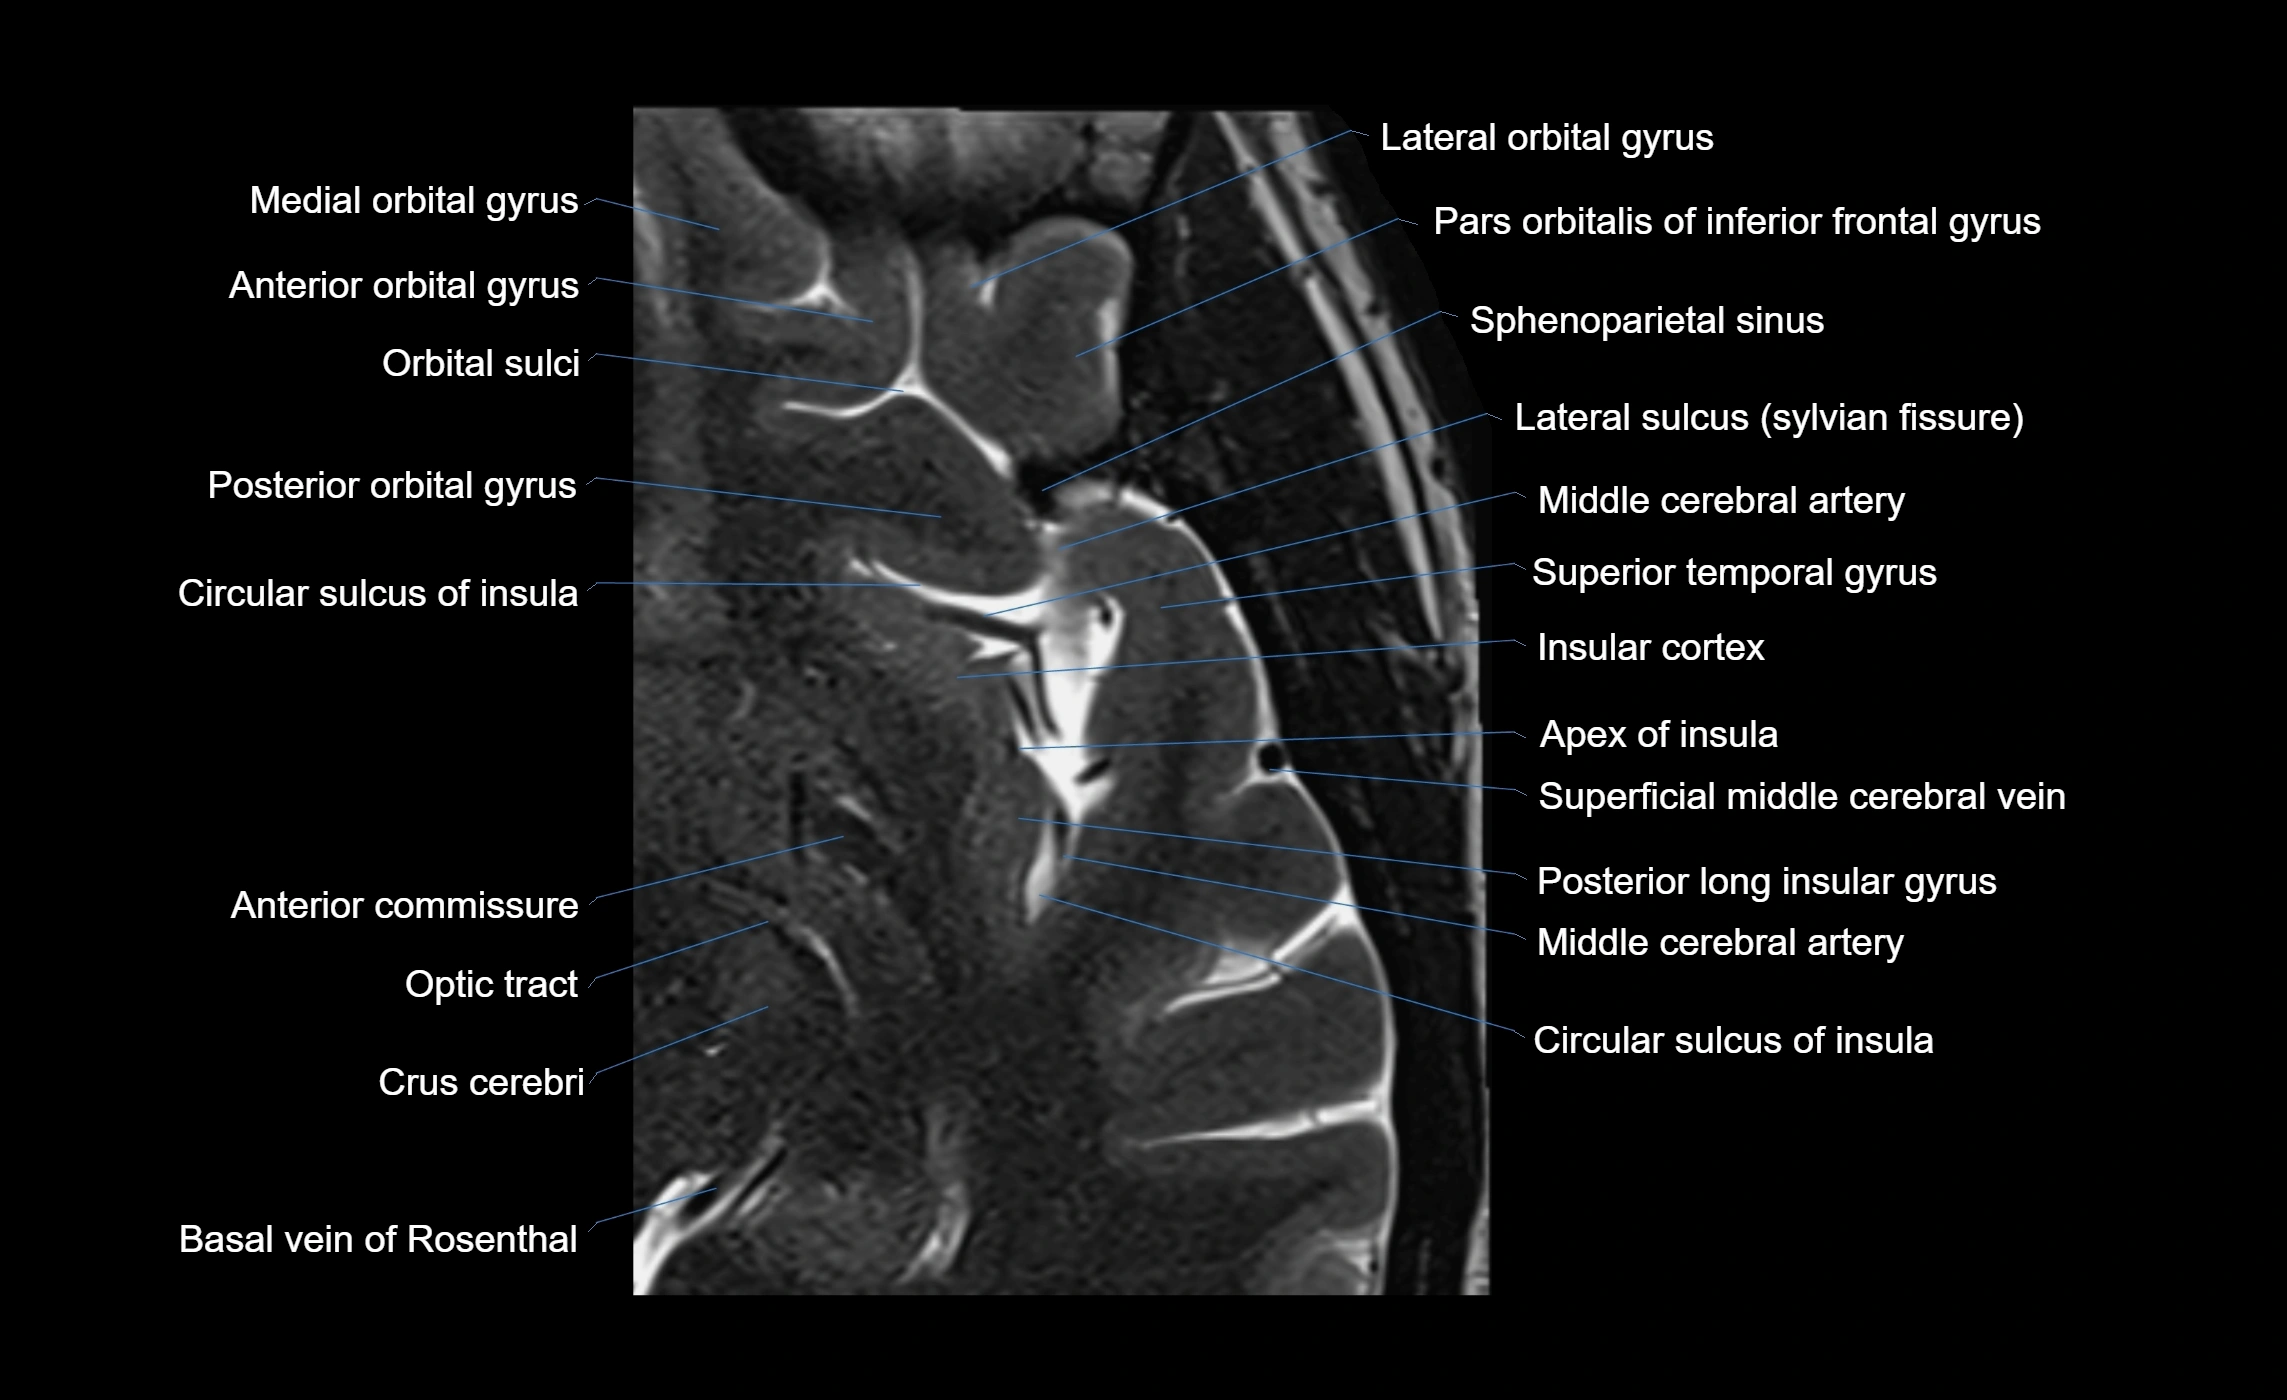

• T1-weighted imaging:

• The Sylvian fissure and its anterior ascending ramus appear as low-signal intensity (dark) CSF-filled clefts between the gyri.

• Clear demarcation between adjacent gray and white matter.

• T2-weighted imaging:

• The fissure, including the anterior ascending ramus, is hyperintense (bright) due to CSF signal.

• Better visualization of the separation between opercular and triangular parts of the inferior frontal gyrus.

• FLAIR imaging:

• The ramus is visualized as a linear dark space (suppressed CSF signal) between the surrounding cortex.

• Adjacent cortical and subcortical abnormalities (e.g., edema or gliosis) can be assessed relative to the ramus.